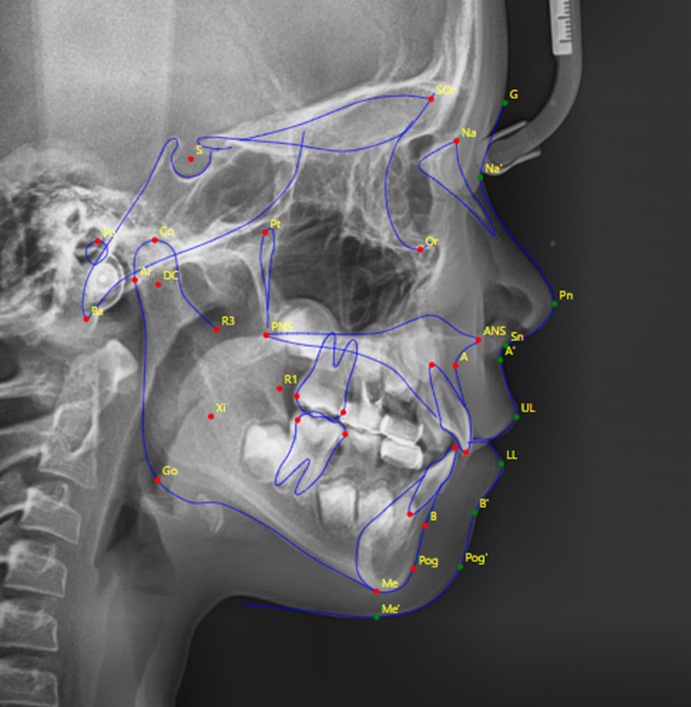

어린이들은 아직 성장이 진행 중이기 때문에, 치열 뿐만 아니라 골격적인 부분에도 다른 문제는 없는지 함께 꼼꼼하게 검진하는 것이 필요합니다.

이렇게 정밀한 검진을 통해 골든타임을 놓치지 않고 제때 필요한 치료를 받을 수 있게 됩니다.

특히 성장판 검사(손목 엑스레이)도 함께 진행하여 현재 아이의 성장 상태를 정확히 파악하는 것이 중요합니다.

이 시기에는 단순히 치아의 위치만 바로잡는 것이 아니라, 턱뼈의 성장 방향과 속도를 적절하게 조절할 수 있습니다.

이러한 골격적 문제를 성장기에 개선하지 못하고 방치할 경우, 성장이 완료된 후에는 교정치료만으로 해결하기 어려워져 외과적 수술이 필요할 수도 있습니다.